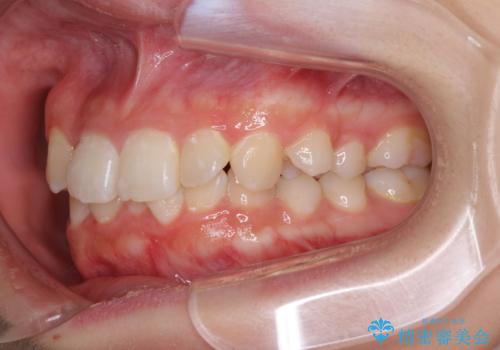

- 八重歯やデコボコをインビザラインで治療したいとのことで来院された患者様です。

インビザライン単体で治療を行うには叢生が強いと判断されたため、事前にワイヤー装置で抜歯矯正を行い、ある程度改善してからインビザラインにて仕上げていくこととしました。